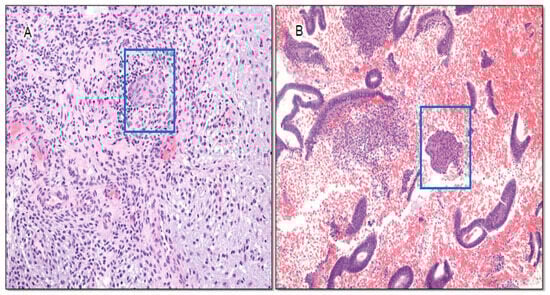

6.2.1. Utility of Three-Marker Panel Plus Morules in AH/EIN in Polyps

6.2.2. Utility of Three-Marker Panel Plus Morules in Secretory AH/EIN

6.2.3. Utility of Three-Marker Panel in Small-Sized AH/EIN

6.2.4. Utility of Three-Marker Panel Plus Morules in the Identification of Residual Lesion in Progestin-Treated AH/EIN

6.2.5. Utility of Three-Marker Panel in Other Putative Endometrial Precancers